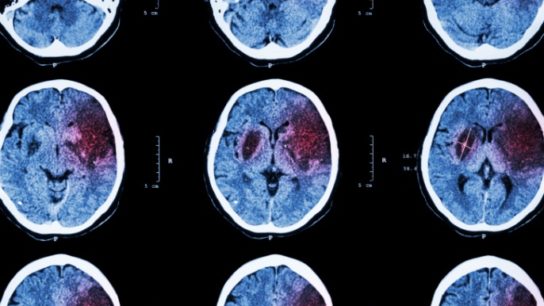

Neuroimaging could enable better classification of patients and provide information on affected brain regions.